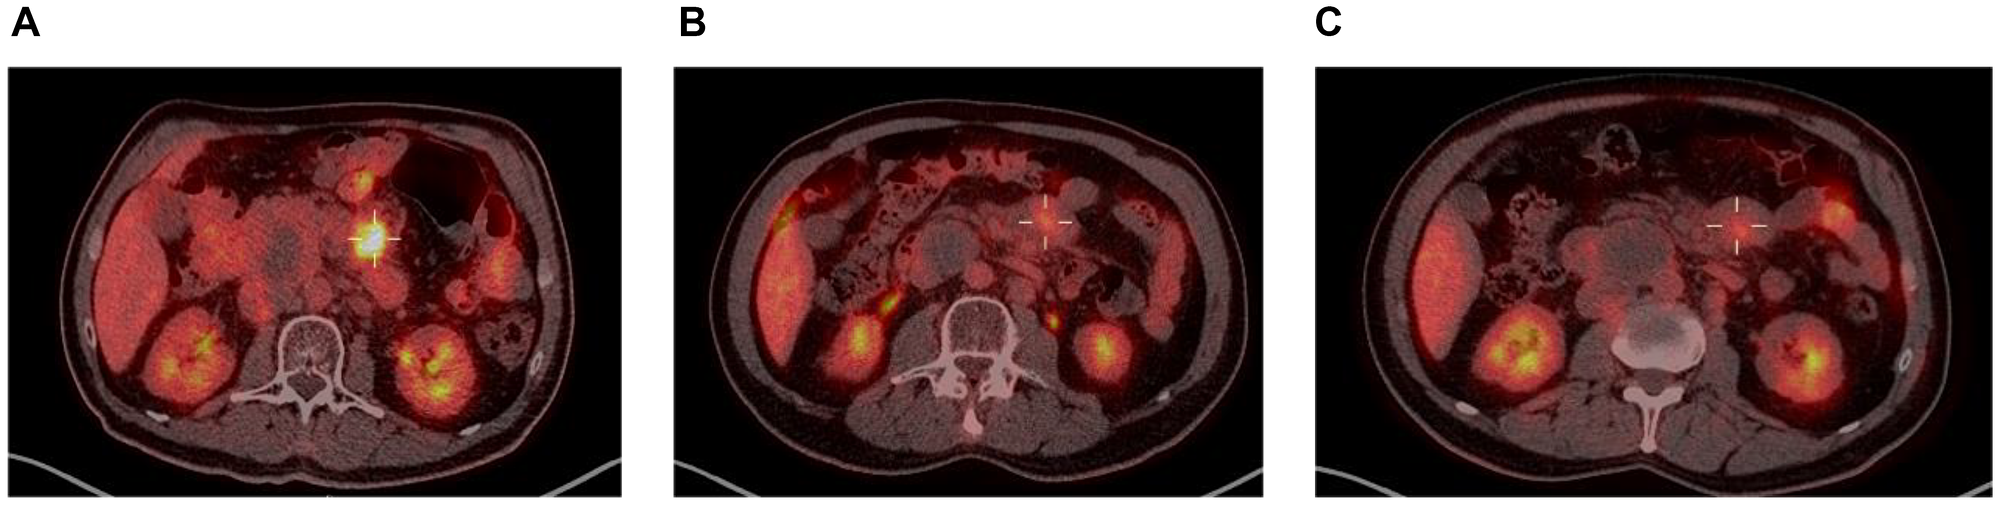

Taking a closer look at those 2 patients, both had localized disease at inclusion (Ann-Arbor stage II), and their responses to enitociclib progressively deepened over time. Partial responses were achieved after 5 and 6 months and complete metabolic responses (CMR) at 7 and 8 months from the first dose received (Figures 1 and 2). These patients stopped treatment (as a result of the COVID-19 pandemic during which follow-up became more difficult) after 20 and 36 months in complete remission, respectively. And after 6.4 and 4.8 years, their CMRs continue to be sustained as of today. These findings are indicative of the antitumor activity of this new CDK9 inhibitor against HGBL. However, it requires time to achieve this effect, likely because the drug’s mechanism of action requires time to fully inhibit the production of short-lived proteins and thus induce clinical responses.

Figure 1: PET scan at screening (A), 5 months (B) and 8 months on treatment (C).